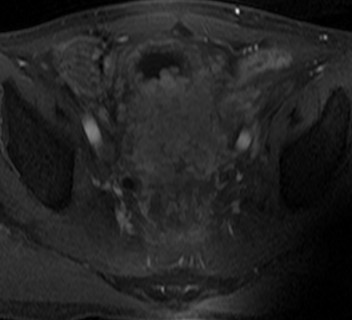

患者男性,63岁。诊断:直肠癌术后Ⅳ期,膀胱、盆腹腔及骨多发转移。患者2013年3月确诊后,行放化疗,后吃中药治疗,2015年12月病情恶化。2016年1月,盆腔MRI检查提示直肠癌侵及膀胱及周围组织,伴骶前转移及骶骨转移。2016年3月,CT检查提示直肠占位病变伴膀胱、前列腺、部分骶椎输尿管受侵,右侧大网膜强化结节,转移不除外,肠系膜及腹膜后淋巴结增大。肠镜检查提示肛管见菜花样肿物,肛管狭窄。化疗一疗程后,患者不能耐受而终止。为寻求下一步治疗方案,患者找到全球肿瘤医生网A45专家,经过中美癌症专家综合会诊,制定A45治疗方案。

患者于2016年6月开始A45治疗,一个疗程后复查,膀胱及直肠病灶明显缩小,肛周复发灶较前缩小,血尿症状消失,疼痛症状消失,其他症状显著缓解。